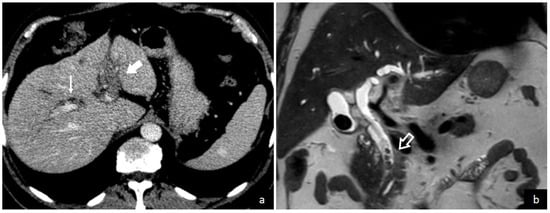

The demonstration of thrombus in the portal vein is the central finding leading to a pylephlebitis diagnosis. Both computed tomography (CT) scanning and abdominal ultrasonography can detect the presence of thrombi in the portal vein as shown in Figure 3 and Figure 4. Ultrasonography can detect the presence of echogenic material in the portal vein lumen, which can be confirmed by flow alterations on Doppler analyses [2,213]. CT scan should be preferred because of its higher definition and the additional investigative ability to identify possible abdominal or pelvic infective foci [2,39,65]. According to a recent systematic review, which enrolled studies between 2010 and 2021, the diagnosis was determined with a CT scan in 89.3% of patients and an ultrasound examination in 38.8% of patients [208]. In contrast, a previous review which included studies before 2010, found that CT scan was used only in 51% of patients. Magnetic resonance imaging (MRI) [44,210], angiography [69,91,217], endoscopic ultrasound [81], or positron emission tomography (PET) [5,42] can also be used to demonstrate portal vein thrombosis; however, their application remains limited to selected cases.

Figure 4.

A 68-year-old male was admitted to the emergency department of Trieste University Hospital with symptoms and laboratory tests consistent with hepato-cholangitis. Contrast-enhanced CT image (a) shows the absence of opacification of the left intrahepatic portal vein branch (solid arrow) due to portal vein thrombosis and mild biliary dilation (thin arrow). Coronal T2 weighted MR image (b) demonstrates multiple filling defects (empty arrow) in the distal common bile duct consistent with choledocholithiasis and biliary sludge.